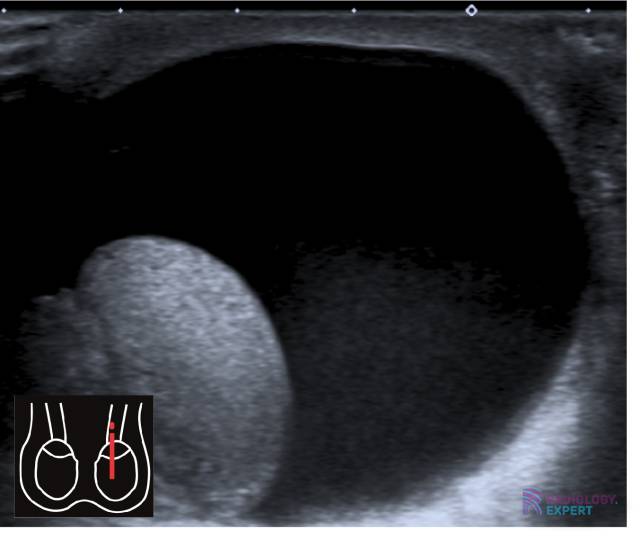

Echo scrotum; hydrocèle. Echo scrotum; hydrocèle.